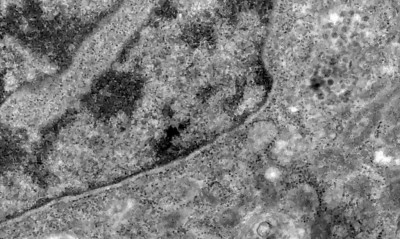

Pesquisadores brasileiros conseguiram, pela primeira vez, detectar a presença do coronavírus em retinas. O estudo pode contribuir para compreender melhor a dinâmica do vírus e as sequelas em pacientes infectados.

Os pesquisadores analisaram retinas de pacientes que morreram em decorrência da covid-19 e compararam com fotos dos olhos desses pacientes quando vivos para analisar as diferenças e formas de aferir a presença do vírus a partir da retina.

Segundo o professor da UFRJ e um dos coordenadores do estudo Rubens Belfort Jr, a retina é um biomarcador importante, pois faz parte do sistema nervoso, mas é mais acessível, permitindo identificar a presença do vírus em determinados locais do corpo, como nesse sistema.